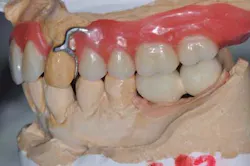

Figs. 6 a, b, c, and d: RPD framework try-in, bite record with mandibular implant-supported metal frameworks and mounting

- Try-in and final bite registration.